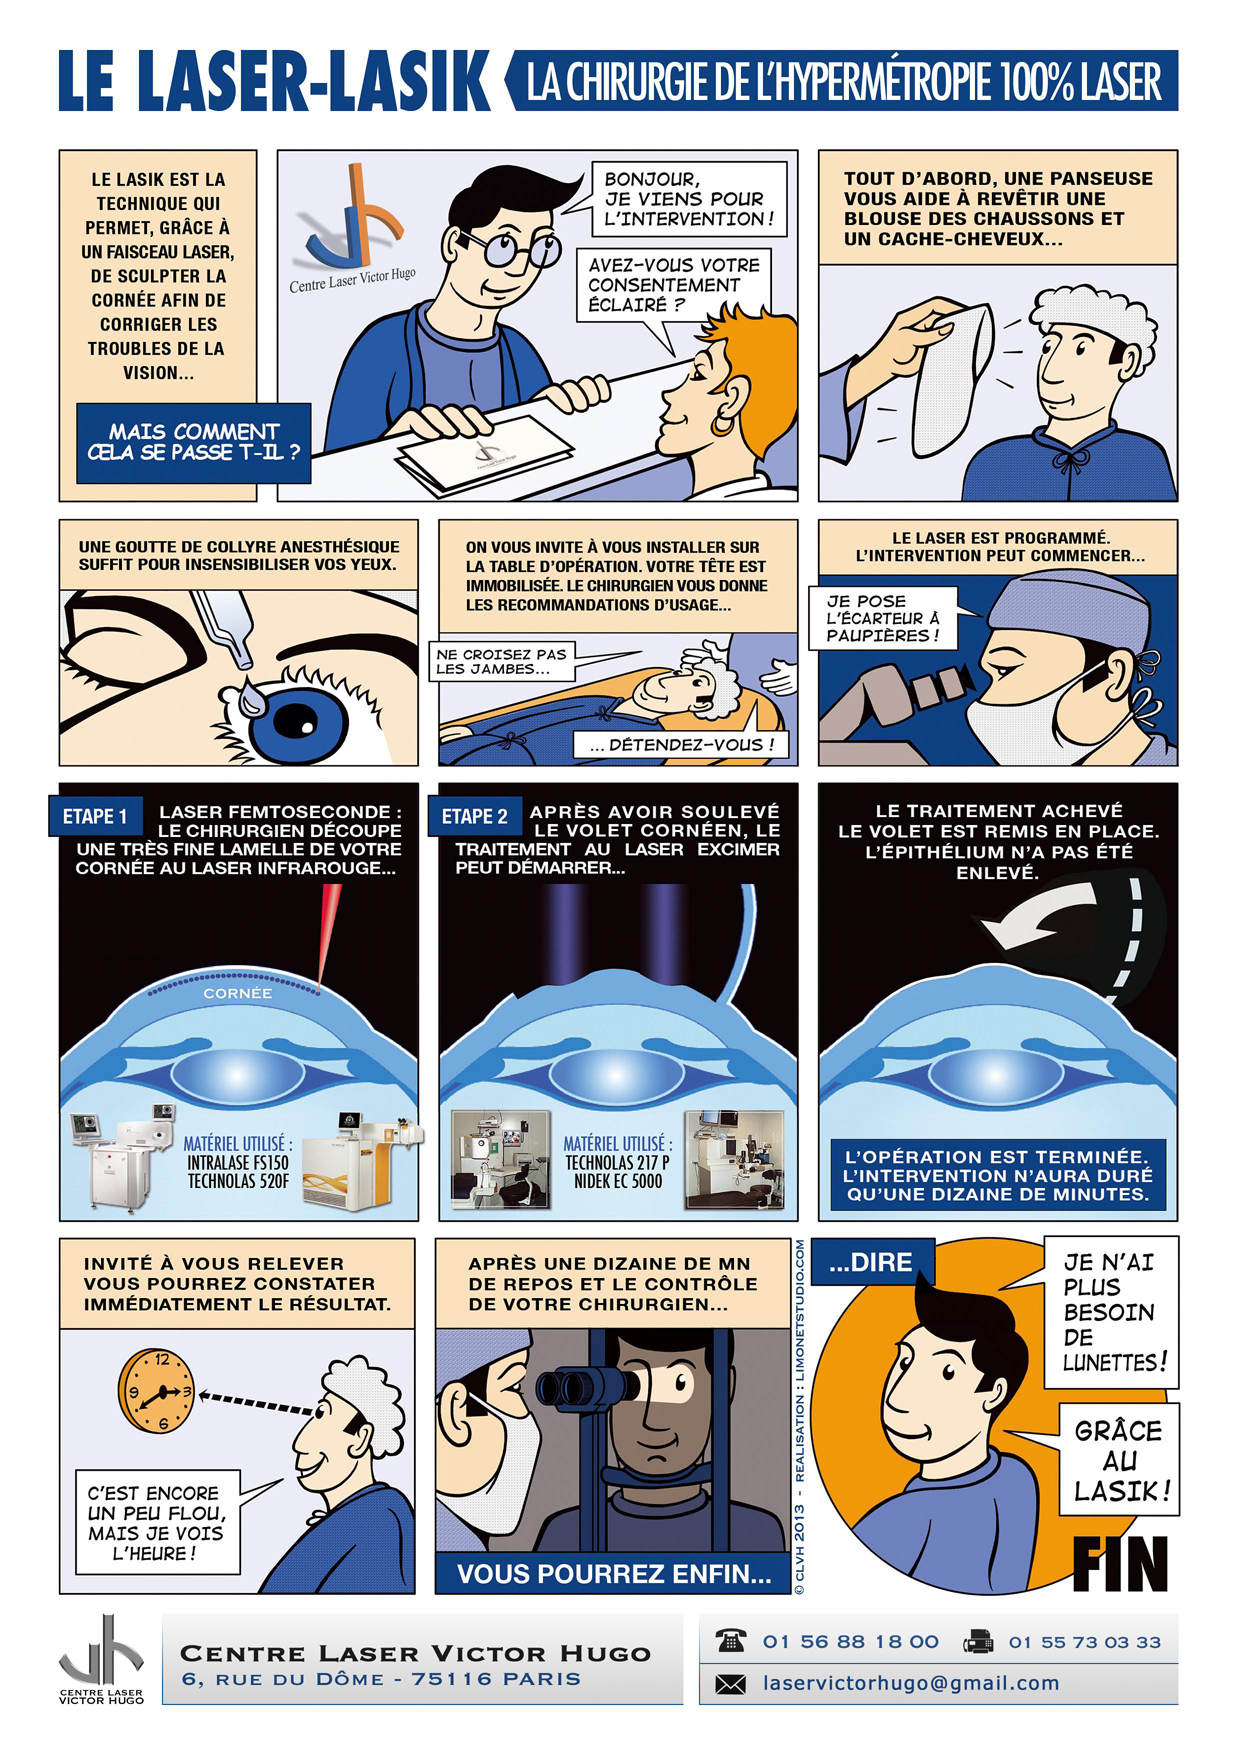

Afin de répondre aux interrogations d'un public de plus en plus intéressé, nous vous proposons cet ouvrage explicatif sous la forme d'une bande dessinée ludique. Cette bédé aborde les troubles de la vision, la chirurgie réfractive (LASIK, PKR et PresbyLASIK), la technique des anneaux et des implants. Cette bébé aborde également l'amblyopie et son traitement orthoptique. Maintenant... à vous de voir !